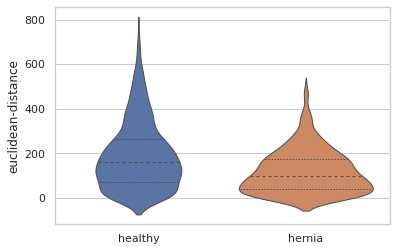

The statistics from the blood vessel branches in the healthy and herniated lung shows clear differences between the two.

Most striking is the difference in the number of blood vessel branches. The herniated lung has less than 40% of the number of blood vessel branches in the healthy lung.

There are also quantitative differences in the sizes of the blood vessels. Here is a violin plot showing the distribution of the distances between the start and end points of each blood vessel branch. We can see that overall the blood vessel branches start and end closer together in the herniated lung. This is consistent with what we might expect, since the healthy lung is more well developed than the lung from the hernia model and the hernia has compressed that lung into a smaller overall space.

EDIT: This blogpost previously described the euclidean distance violin plot as measuring the thickness of the blood vessels. This is incorrect, and the mistake was not caught in the review process before publication. This post has been updated to correctly describe the euclidean-distance measuremet as the distance between the start and end of branches, as if you pulled a string taught between those points. An alternative measurement, branch-length describes the total branch length, including any winding twists and turns.